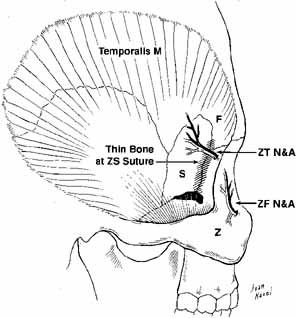

third meets the anterior two-thirds. Trigeminal Nerve (V) The ophthalmic and maxillary divisions of the sensory trigeminal nerve

enter the orbit and pass through to supply the superior two-thirds

of the face (Figs. 19 and 20) . The ophthalmic division enters the orbit through the superior

orbital fissure as three branches: the lacrimal, frontal, and nasociliary. The

lacrimal nerve is the smallest branch, and it passes into the

orbit through the lateral end of the extraconal superior orbital fissure (see Figs. 6 and 19). It joins the lacrimal artery to reach the posterior aspect of the

lacrimal gland. Here, it forms superior and inferior branches; the

former supplies the gland, conjunctiva, and the lateral upper eyelid. The

inferior branch anastomoses with the zygomaticotemporal branch of

the maxillary trigeminal nerve, where it picks up parasympathetic secretory

fibers to the gland. The frontal branch passes just beneath the

periorbita, where it divides anteriorly in the orbit to form the supratrochlear

and larger supraorbital branch, which supply sensation to the

medial canthus, upper lid, and brow areas (see Fig. 19). The supraorbital nerve should be identified and spared during dissection

of the supraorbital rim, transcoronal forehead orbital approaches, or

during forehead lifts. The nasociliary branch of the ophthalmic

division is the only one to pass through Zinn's annulus. It passes

over the optic nerve with the ophthalmic artery to lie between the

superior oblique and medial rectus muscles. The nasociliary nerve gives

off a sensory route to the ciliary ganglion, two or three long ciliary

nerves to the globe, the anterior and posterior ethmoidal nerves

to supply the nasal mucosa, and the terminal infratrochlear branch to

supply the tip of the nose (Fig. 21). Involvement of this terminal infratrochlear branch of the nasociliary

nerve in herpes zoster ophthalmicus is termed Hutchinson's sign.  Fig. 19 Schematic drawing of the trigeminal nerve course in the orbit. (V1, Vl nerve; V2, V2 nerve; V3, V3 nerve; FN, frontal nerve; SON, supraorbital nerve; STN, supratrochlear nerve; LN, lacrimal nerve; ZTN, zygomaticotemporal nerve; ZFN, zygomaticofacial nerve; ZN, zygomatic nerve; NCN, nasociliary nerve; SB, sensory branch to the ciliary ganglion; CG, ciliary ganglion; SPCN, short posterior ciliary nerves; LPCN, long posterior ciliary nerves; PEN, posterior ethmoidal nerve; AEN, anterior ethmoidal nerve; ITN, infratrochlear nerve; ION, infraorbital nerve) Fig. 19 Schematic drawing of the trigeminal nerve course in the orbit. (V1, Vl nerve; V2, V2 nerve; V3, V3 nerve; FN, frontal nerve; SON, supraorbital nerve; STN, supratrochlear nerve; LN, lacrimal nerve; ZTN, zygomaticotemporal nerve; ZFN, zygomaticofacial nerve; ZN, zygomatic nerve; NCN, nasociliary nerve; SB, sensory branch to the ciliary ganglion; CG, ciliary ganglion; SPCN, short posterior ciliary nerves; LPCN, long posterior ciliary nerves; PEN, posterior ethmoidal nerve; AEN, anterior ethmoidal nerve; ITN, infratrochlear nerve; ION, infraorbital nerve)